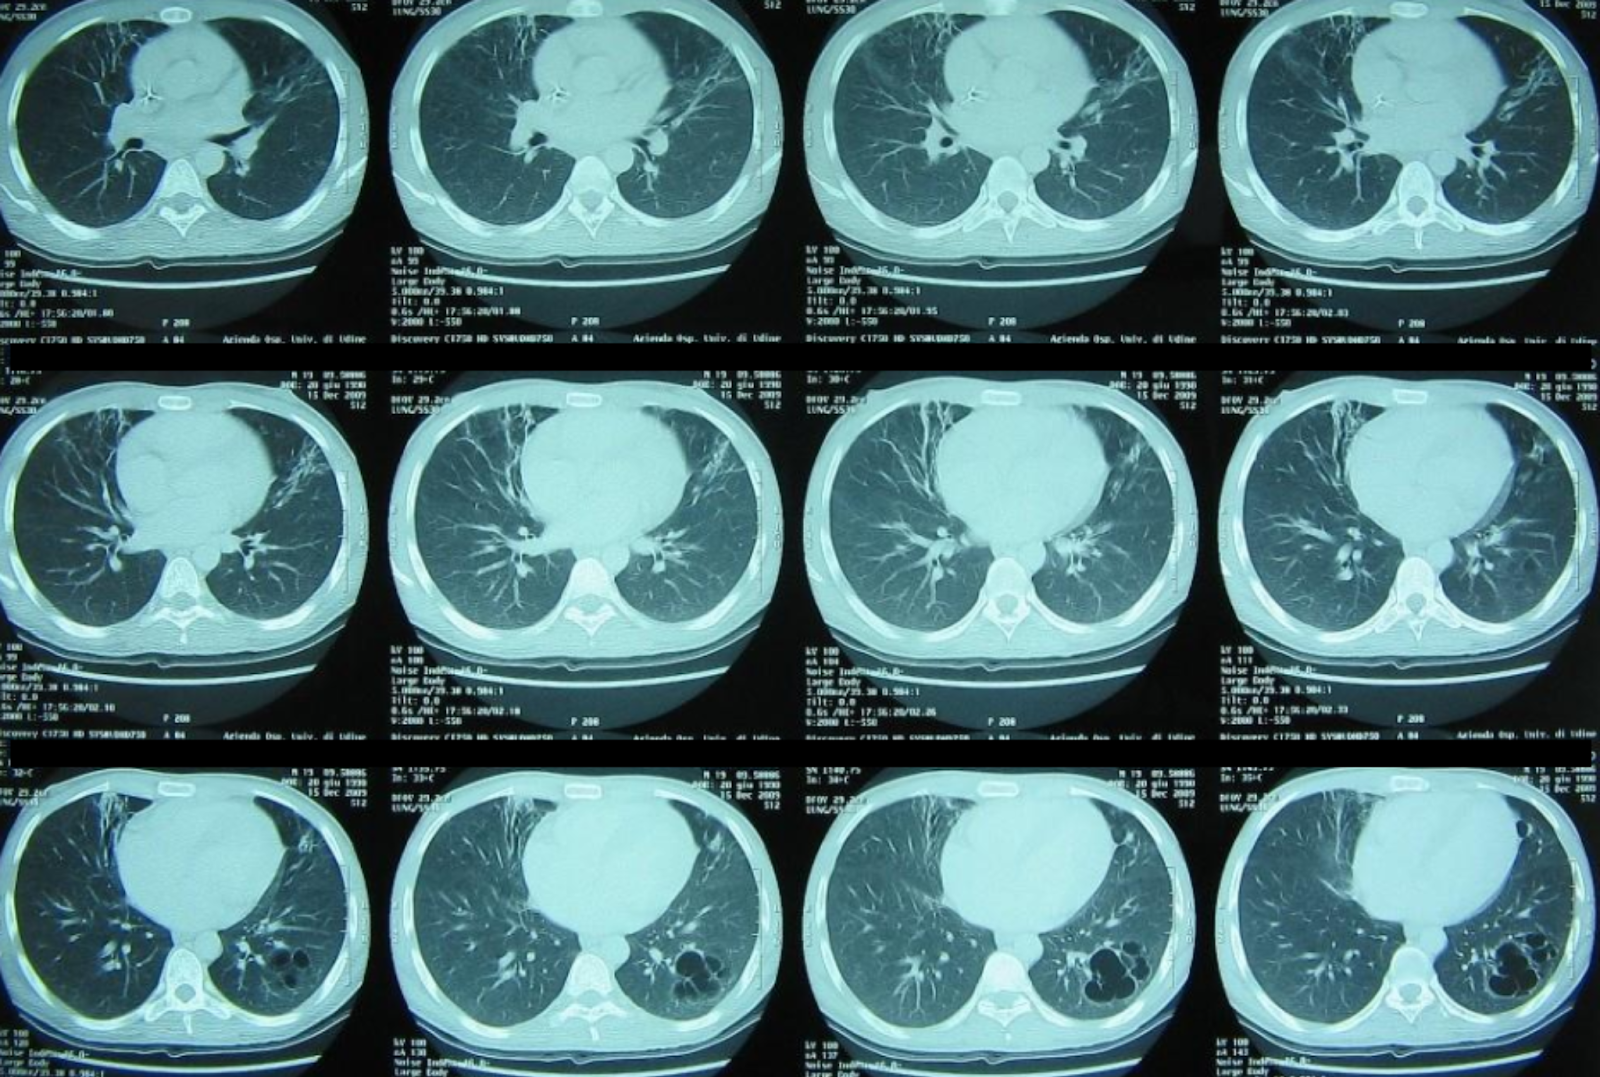

Follow-up chest CT showing partial radiological improvement following targeted non-conventional therapy.

Final diagnosis and clinical outcome

As the diagnostic work-up was further expanded in light of the patient’s refractory course, a unifying explanation finally emerged. Given Daniel’s West African origin, the early gastrointestinal symptoms preceding respiratory failure, and the precipitous progression to severe ARDS, the search for atypical and parasitic pathogens was intensified.